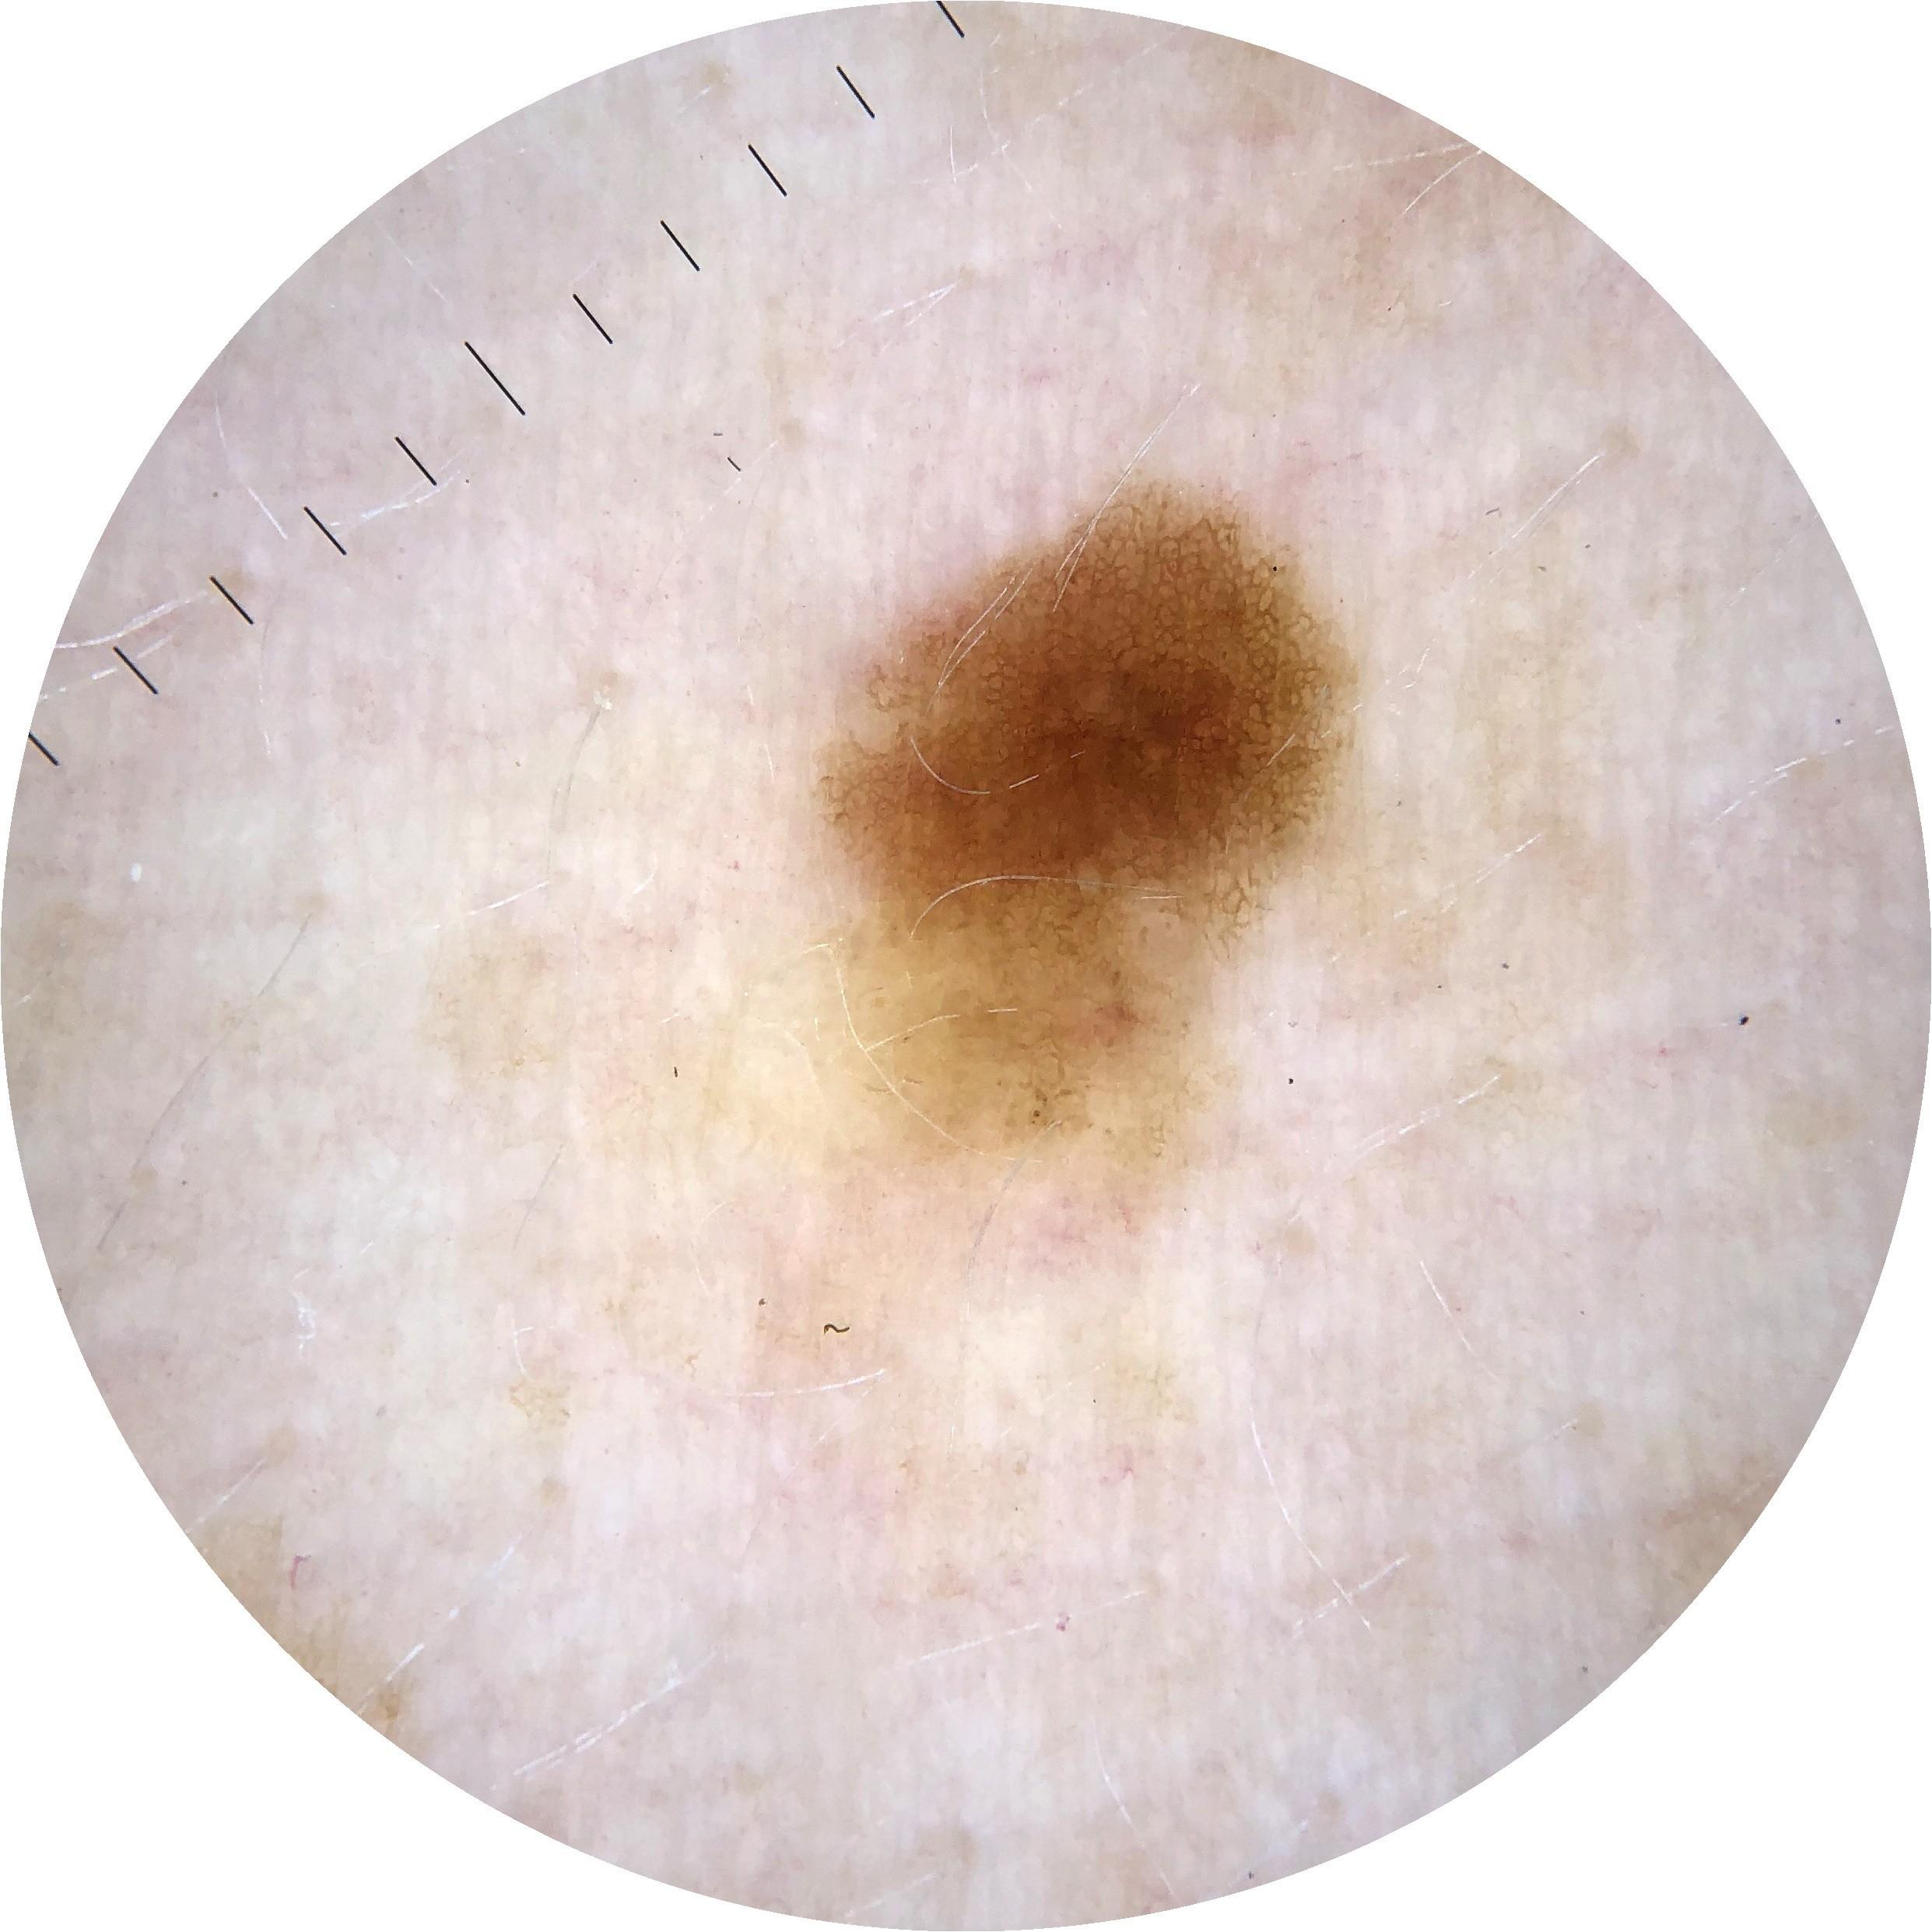

ISIC_8528385

Clinical

acquisition_day 27

age_approx 60

anatom_site_1 Upper extremity

diagnosis_1 Benign

diagnosis_confirm_type single image expert consensus

fitzpatrick_skin_type I

image_type dermoscopic

sex female